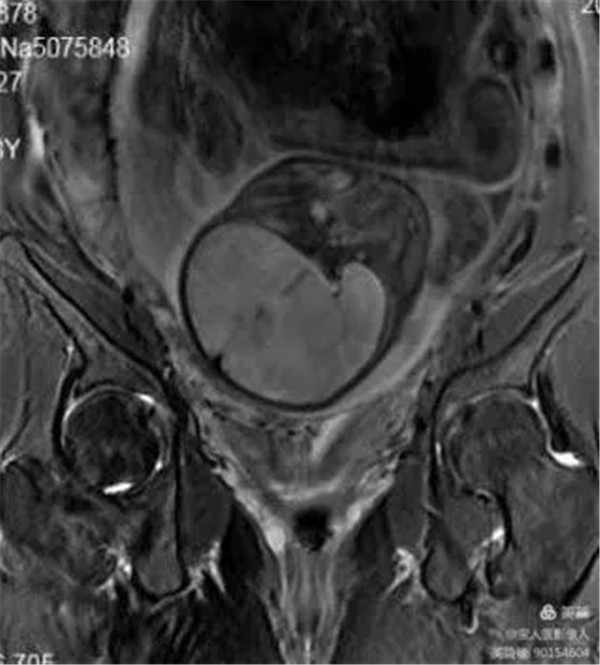

病例11:患者前置胎盘、血管前置、胎盘穿透性植入

图2,冠状位-显示胎盘与子宫左右肌壁、宫颈关系。